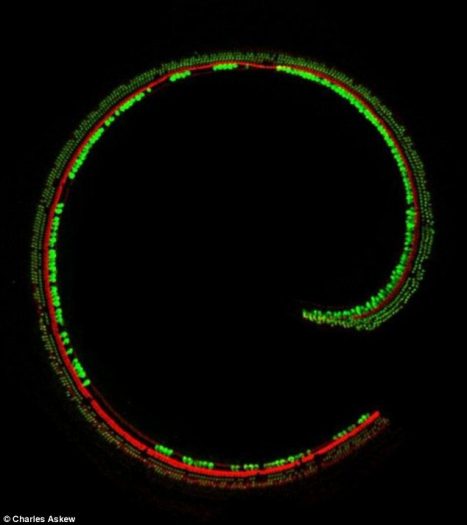

در داخل گوش زواید مو مانندی رو سلولهای عصبی مودار قرار دارد که صدا را به سیگنال های الکتریکی قابل تفسیر برای مغز تبدیل می کند. جهش ژنتیکی در DNA می تواند قابلیت تبدیل صدا به سیگنال را از این موهای گوش بگیرد و همین امر منجر به ناشنوایی کامل یا جزیی می شود.

محققان برای حل این مشکل، یک ویروس خاص را به گونه ای اصلاح ژنتیکی کرده اند که سلول های مو را تصحیح می کند و قابلیت تبدیل صدا به سیگنال را به موهای مخصوص گوش باز می گرداند. اصلاح عملکرد موهای گوش با تزریق این ویروس به گوش انجام می شود. نتایج اولیه این آزمایش روی موش های آزمایشگاهی با موفقیت انجام شده است.